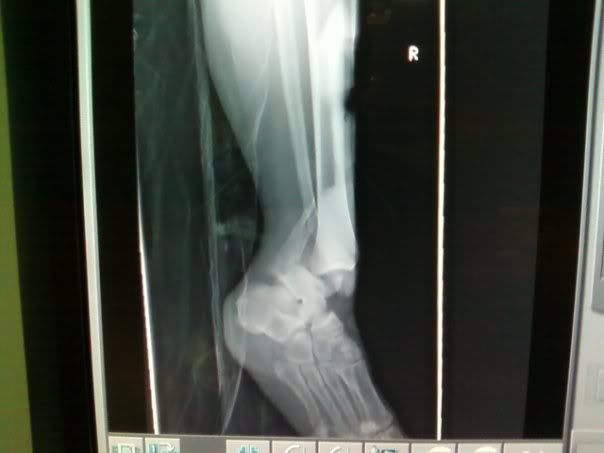

A Derby Revolution of Bakersfield skater "Imma Cougar" sustained an awful injury at Red Red this past weekend. She broke her ankle in two places and dislocated it. She is a single mother of two small children (with Christmas right around the corner) and can't work due to her injury. She is scheduled to have surgery and is going to be charged $1000 for the surgery and $1500 for an implant in her leg. We are trying to reach out to the derby community (and anyone else that can help) Please help our fellow sister out with anything you can. We have set up an account through Paypal. DONATE TO IMMA COUGAR AT WWW.PAYPAL.COM SEND PAYMENT TO HELPIMMACOUGAR@